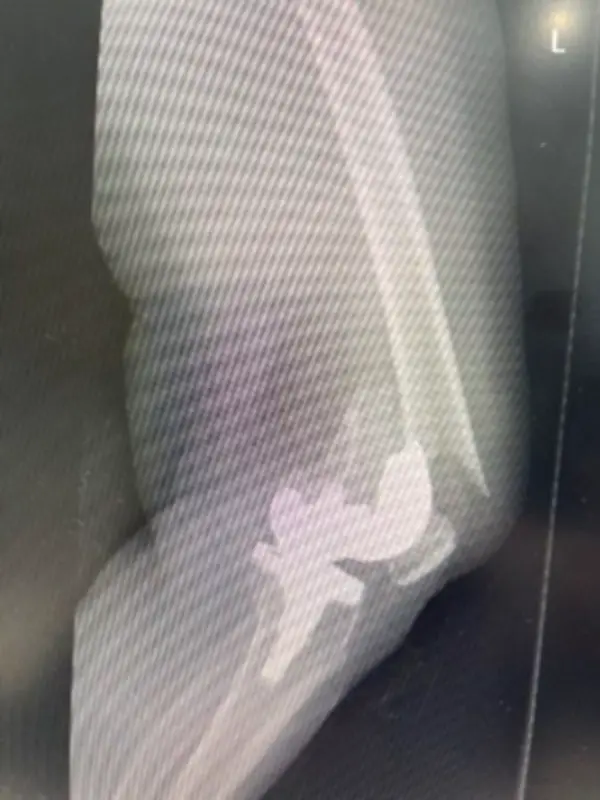

في إنجاز طبي بارز، نجح فريق طبي متخصص في مستشفى المانع – العزيزية، تحت قيادة الدكتور النابغة المليح، في استعادة قدرة مريضة تبلغ من العمر 83 عامًا على المشي، بعد أن تعرضت لكسر معقد حول مفصل ركبة صناعي قديم. جاءت هذه الإصابة نتيجة سقوط مباشر على الركبة، مع وجود حالة من هشاشة العظام التي زادت من تعقيد الحالة.

خضعت المريضة لعملية جراحية دقيقة شملت مراجعة كاملة للمفصل، حيث تم استبدال الجزء السفلي من عظمة الفخذ. بعد أربعة أسابيع فقط من الجراحة، تمكنت المريضة من المشي بحرية وتحمل الوزن بشكل طبيعي، مما يعكس نجاح الخطة العلاجية المتبعة.